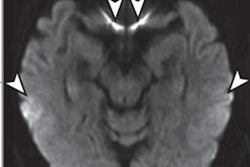

The investigators noted in their poster presentation of these findings that the cingulate, insular, parietal, and posterior temporal cortices and the striatum are preferentially affected on brain MRI; hence, if radiologists are familiar with these characteristics, it might improve the accuracy of CJD diagnosis.

"The message is the importance of education -- to get people to consider CJD as a diagnosis," said Katherine Wong, Geschwind's research coordinator, who presented the poster at the AAN conference. "A lot of the outside reports didn't even note areas of hyperintensities that were obvious to those who know what to look for."